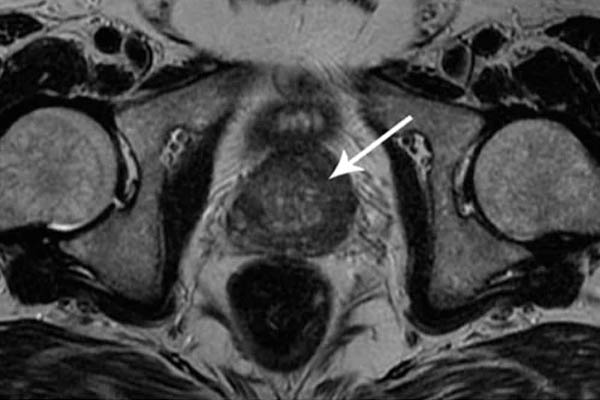

Saya ingin menunjukkan beberapa foto tentang apa yang terjadi pada sistem genitourinari dan organ dalam lainnya dari seorang pria ketika dia berhenti berhubungan seks.

Kanker prostat. Ini didiagnosis pada seorang pria berusia 58 tahun. Alasannya adalah penahanan nafsu dalam jangka panjang (dari usia 51). Pria itu meninggal.